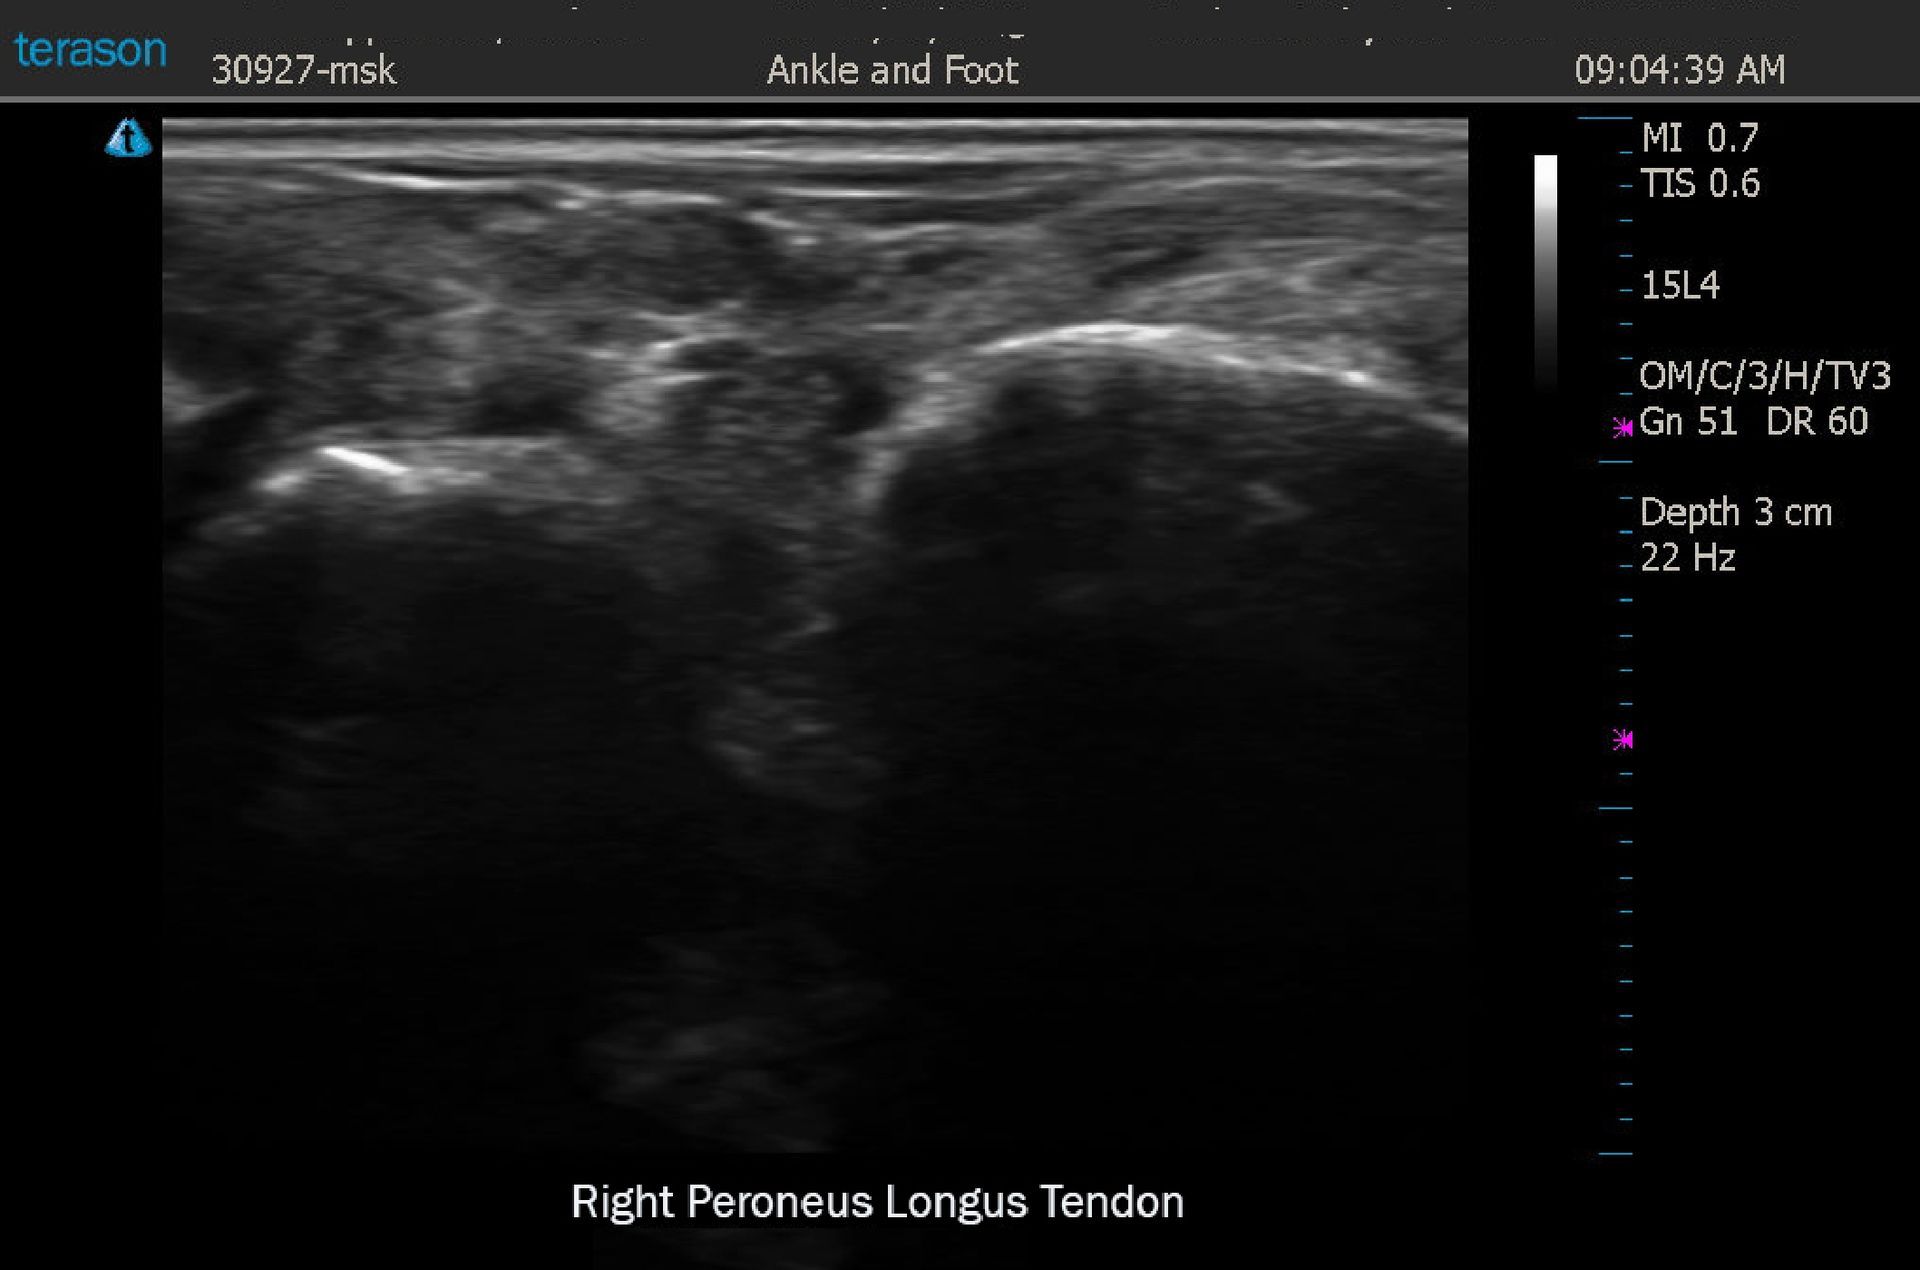

52 yo female with a chief complaint of RLE pain, numbness and cold sensations involving the entire limb after twisting her ankle. MRI showed subtalar effusion and peroneus longus and brevis tendinosis. DX US confirmed peroneus longus tendinosis. Cold stress sympathetic skin response thermology showed an asymmetry pattern over the dorsal aspect of the foot, distal leg, and lateral thigh. Thermographic impression was RLE sympathetic pain syndrome tracking in a L5 distribution.